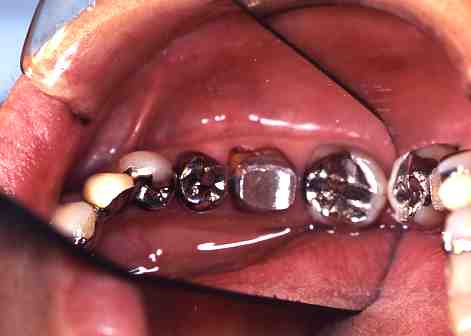

【歯科一般】

(3)虫歯の治療(その3)

1.根っ子しかないと思って

あきらめてはいませんか?

(*この症例は、根の治療が

終わっております)

2.土台をたてて...

3.冠をかぶせることができます。